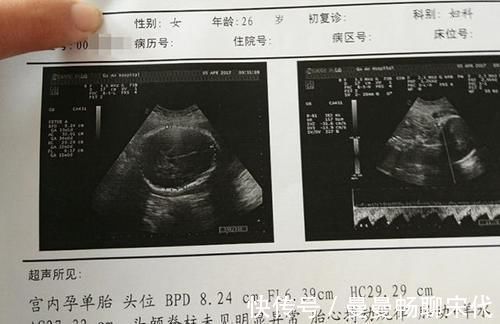

女性在怀孕后,随着孕期的进程,自身和胎儿的体重相应会有所增加,通过孕检的各项数据指标,医生能掌握胎儿的发育情况,从中判断出胎儿的体重是否正常,对孕妇控制体重提供帮助。

因此,孕妇要重视孕期检查,听取医生的合理化建议。